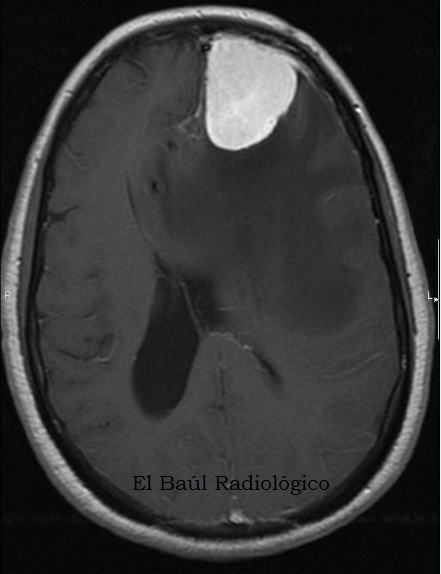

FIGURA 1+C) Imagen obtenida después de administrar 100 cc de contraste yodado endovenoso. La lesión es tan hiperdensa que podría confundirse, a simple vista, con un osteoma u otra tumoración ósea. ¡ Cómo ha cambiado la situación ¡ Gracias al efecto del contraste las dudas diagnósticas se han disipado)

(Image obtained after administration of 100 ml of intravenous iodinated contrast. The lesion is so hyperdense that could be confused, at first, with an osteoma or other oseous neoplasm. The situation has changed, thanks to the contrast effect and diagnostic doubts have dissipated) ).

Diagnóstico definitivo: Meningioma (Tumoración bien delimtada, anclada en la tabla interna del cráneo que se realza intensamente con contraste yodado). Estos tumores, aunque se localizan fuera del parénquima cerebral producen edema vasogénico, al destruir el endotelio de los vasos periféricos del parénquima cerebral que comprimen. Por tanto ante el hallazgo de una extensa zona de edema vasogénico digitiforme en una exploración de TC hay que pensar también en un meningioma.

(Final diagnosis: Meningioma (well-defined tumor, anchored in the inner table of the skull that enhances intensely with iodine contrast). These tumors, are located outside of the brain parenchyma and produces vasogenic edema, destroying the endothelium of vessels by compressing the brain parenchyma. So when we discover a large area of digitiform vasogenic edema in a CT scan, we must also think in a meningioma)